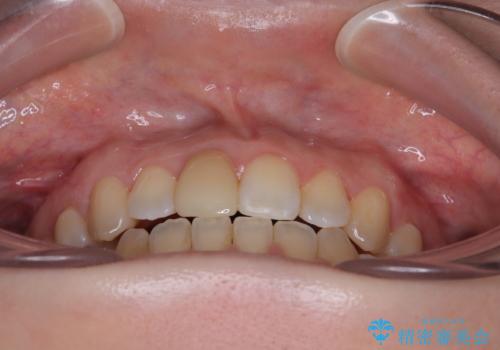

【モニター】後戻りでできた隙間 ワイヤー装置での再矯正

- 学生時代に行った抜歯矯正の後戻りで、隙間ができてしまったことを気にして来院された患者様です。

上顎歯列は歯の移動量が少なかったため、セラミッククラウンは装置を装着せずに治療を終えることができました。